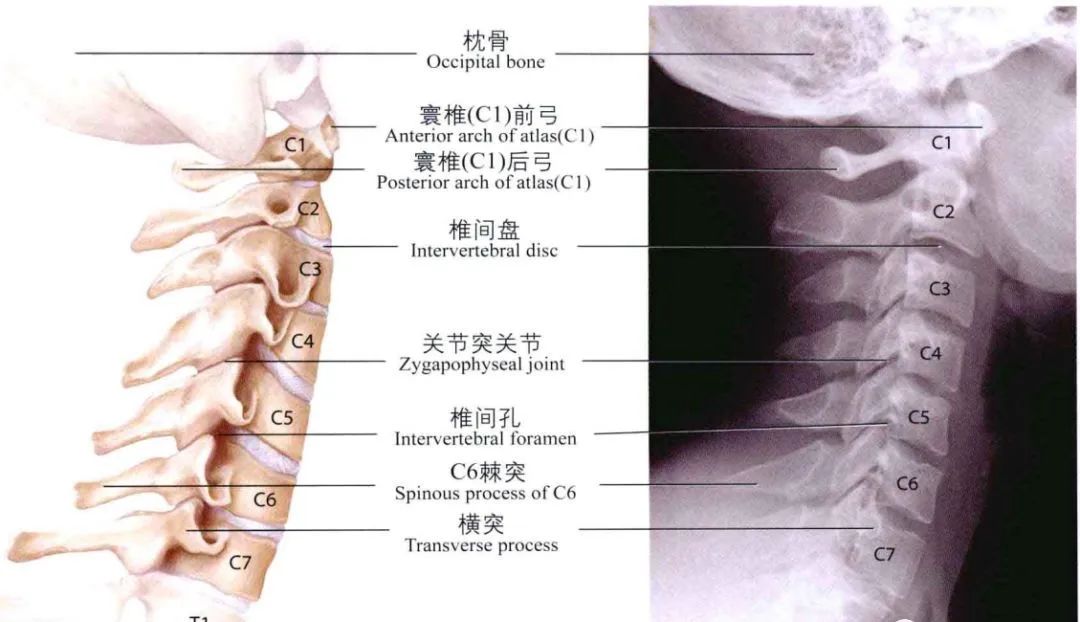

从影像学来看颈椎病为何会引起眩晕